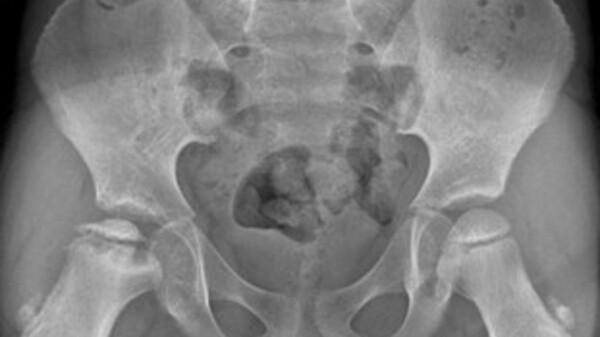

La diagnosi è radiografica e prevede l’esecuzione di una Rx bacino + la proiezione assiale dell’anca coinvolta. La radiografia è importante anche per la stadiazione e la valutazione dell’evoluzione della malattia.

Figura 1: In questa radiografia la malattia è progredita fino al collasso della testa del femore.